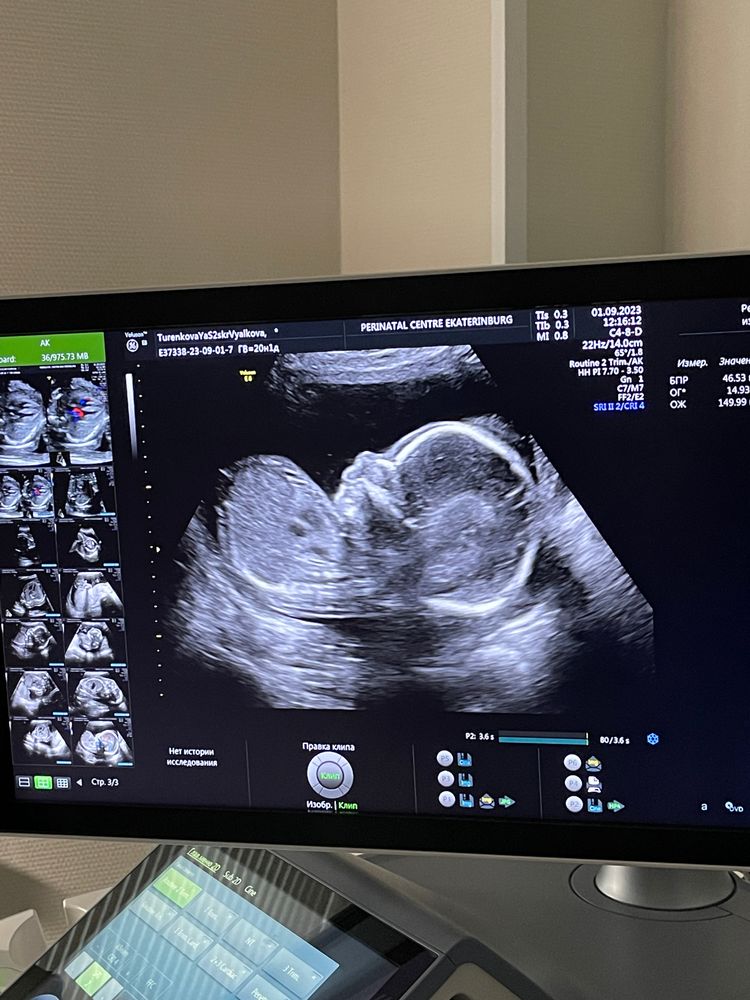

Пишу этот пост на память. Сегодня была на 2 скрининге, с малышом все отлично! Такой красивый, фото правда не удачное мне дала сделать врач. Показал личико не с первого раза, отправляли покушать и ходить. В 12 недель я сдавала кровь на определение пола малыша, когда узнала, что будет мальчик, очень расстроилась, потому что хотела двух сестричек, а потом уже мальчика, но сейчас я безумно рада, что будет именно мальчик. Осталось только убедить мужа на имя которое мне безумно нравится.

Поздравляю! И просто как досужее рассуждение: если это неудачная фотка, то я вам иак скажу: моя мадама пряталась и крутилась так, что у меня есть размытые две фотки которые удалось поймать и фотка, где видно только ухо))))

Грейси, Спасибо огромное! У меня эта врач и в первую беременность делала скрининги, очень хорошая женщина, она пока не найдет хорошее положение лица, не отстанет 😂

Там просто она делала другой кадр прям выразительный, но на главный экран вывела именно этот, я и подумала почему мне дали не лучший кадр, всеровно очень рада увиденному 😁